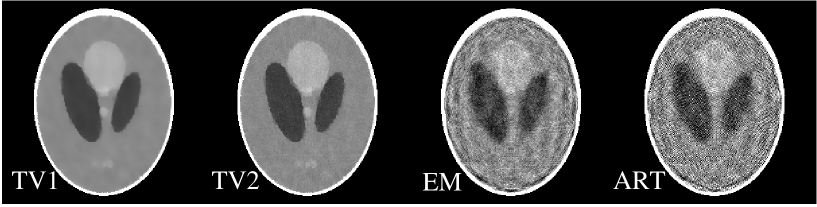

Using the Shepp-Logan phantom with a wavy background in Fig. 11, we generated projection data at 20 views specified by Eq. (19). The amplitude of the wavy background is 1% of the gray matter attenuation coefficient. Any negative values in the phantom are thresholded to zero, so as to allow the applicability of the EM algorithm. With the wavy background the number of non-zero pixels in the gradient image jumps to 51,958 , but the majority of these non-zero values are small compared to the gradients at the boundaries of the different tissues. As was the case with the previous few-view study, the number of measurements is 10,240, which is less than twice the number of non-zero pixels in the gradient image, violating the sparseness condition.

In Fig. 11, we show the images reconstructed by use of the TV, EM, and ART algorithms from the 20-view data. The iteration numbers for obtaining these results were 200, 1000, and 500 for the TV, EM, and ART algorithms, respectively. The images in Fig. 11 indicate that the TV reconstruction is visually almost indistinguishable from the true image and that the EM and ART algorithms have difficulty with this data set. Upon further inspection of the image profiles, it can be seen that the TV algorithm does not yield an exact reconstruction. The small violation, however, of the gradient image sparseness does not appear to lead to large errors in the reconstructed image. We point out once again that this example does not constitute a mathematical proof, but it is suggestive of the conclusion that small violations in the gradient sparseness yields only small errors in the reconstructed image.

For the few-view study, we show in Fig. 13 images reconstructed by use of the TV (labeled TV1 and TV2), EM, and ART algorithms. The iteration numbers for the TV, EM and ART images are 200, 200, and 100, respectively. In the studies with consistent data above, the differences between the TV1 and TV2 images were numerically negligible. With inconsistencies resulting from data noise, however, there is a marked difference. The image after the gradient descent phase is clearly a regularized version of the image obtained after the data projection and positivity constraint. Depending on the task, either image may prove useful for a particular imaging application. For the few-view study, both images and obtained with the TV algorithm appear to have less artifacts than the EM and ART reconstructions in Fig. 13. We point out again that no explicit regularization is performed with EM or ART in the studies here and below aside from the fact that we truncate the iteration numbers at 200 and 100 in the EM and ART algorithms, respectively.